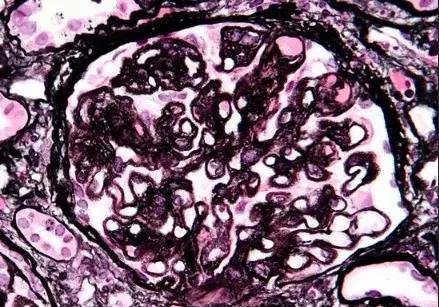

Nefropatía Membranosa: ¿Y si el paciente no responde al tratamiento inicial?

Nefropatía Membranosa: ¿Y si el paciente no responde al tratamiento inicial?

En este video, abordamos estrategias para tratar a pacientes con nefropatía membranosa que no responden al tratamiento inicial. Se enfatiza la importancia de la reevaluación constante y del ajuste del régimen de tratamiento en función de los resultados y del estado del paciente.

Cómo tratar la Nefropatía Membranosa de manera práctica

Cómo tratar la Nefropatía Membranosa de manera práctica